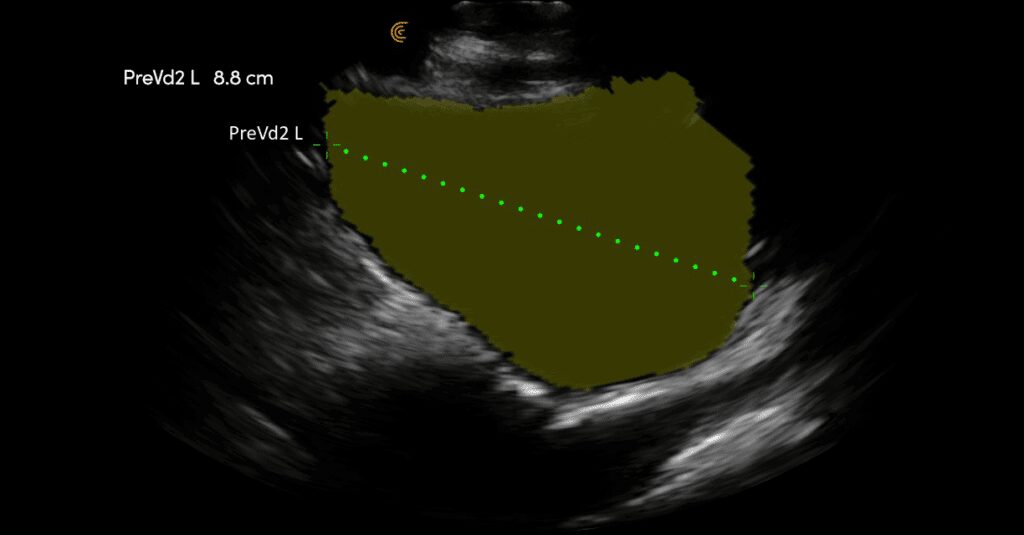

The image quality is amazing, it’s easy to use, and perfect for assessing muscles involved in maintaining continence.